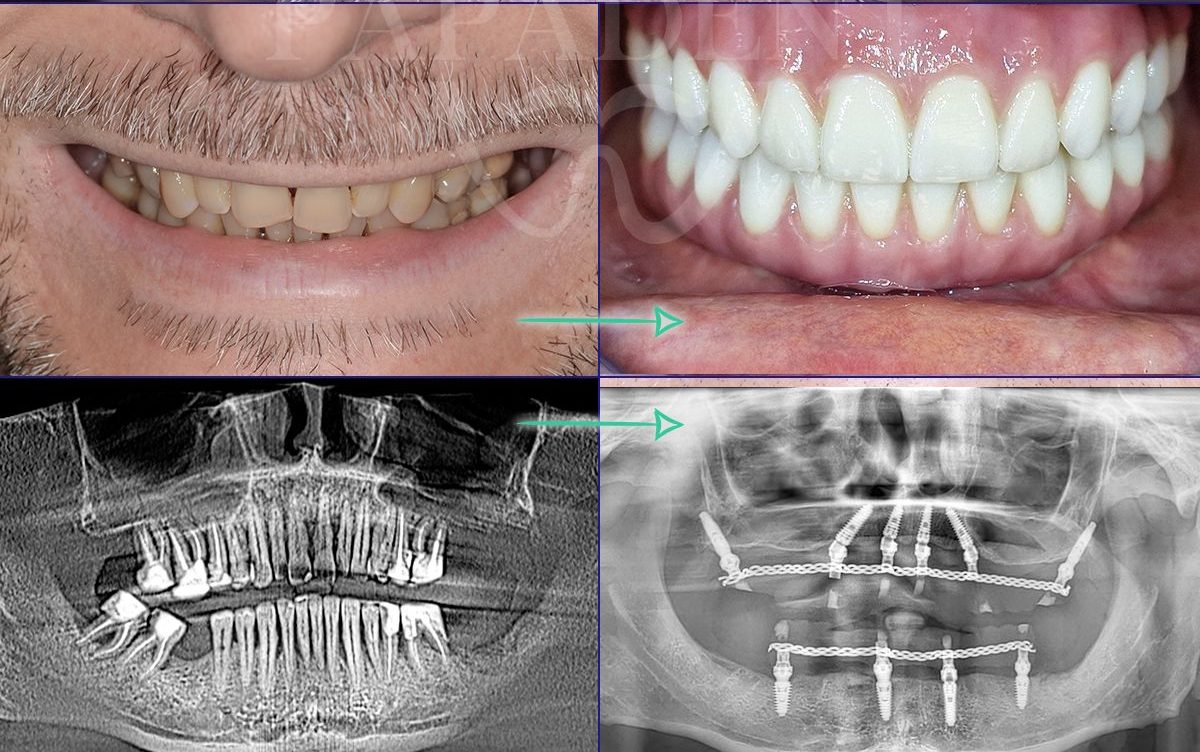

„All-on-4“ yra pažangi dantų implantavimo technika, leidžianti atkurti visą viršutinio arba apatinio žandikaulio dantų lanką vos su 4 implantais. Ant šių implantų fiksuojamas nuolatinis dantų protezas, kuris užtikrina ne tik estetišką šypseną, bet ir pilnavertę kramtymo funkciją. Šis metodas yra greitas, komfortiškas ir daugelio specialistų pripažįstamas kaip vienas efektyviausių sprendimų bedančiams žandikauliams netekus daugelio ar visų dantų.

- „PAPADENT“ gydytojai atliko šimtus sėkmingų operacijų. Gyd. Tomas Stumbrys – „All-on-4“ metodikos specialistas nuo 2014 m.

- Dantų protezai ant 4 implantų vos per 24 – 48 val. Ir turite naujus visus dantis!